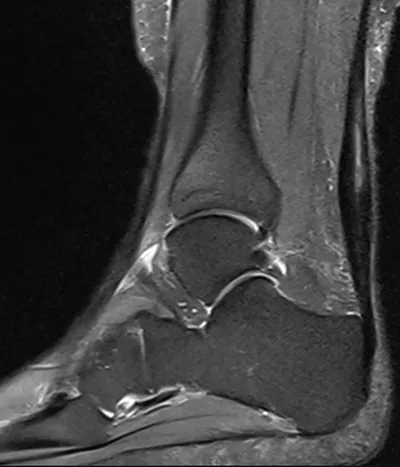

Achilles Radiology Images

- This collection contains 3 radiology images related to achilles, including various imaging modalities such as X-rays, MRIs, CT scans, and ultrasound images commonly used in medical diagnosis and education.